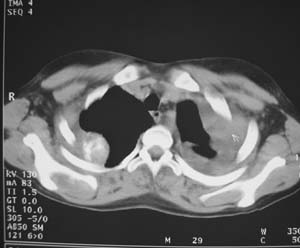

女性,17岁,一年前因股骨病变截肢,现胸憋。

左肺巨大肿块,内散在斑点状高密度骨化影,右肺见多发结节灶,双侧胸膜局限性增厚。有骨肉瘤病史,支持骨肉瘤手术后转移。